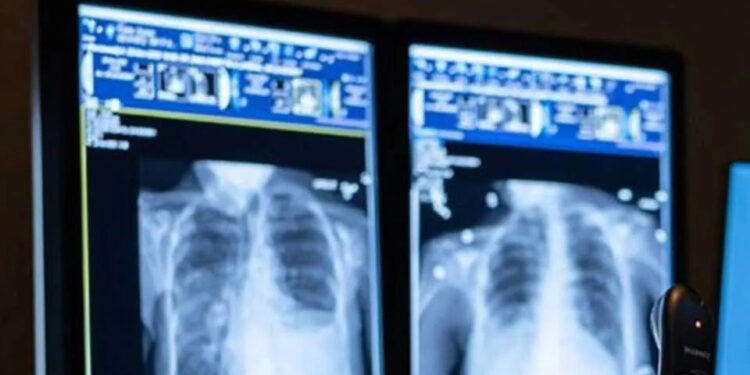

රජයේ රෝහල්වල 530කට ආසන්න විකිරණ තාක්ෂණවේදීන්ගේ හිඟයක් හටගෙන තිබේ.

රජයේ විකිරණ විද්යා තාක්ෂණවේදීන්ගේ සංගමයේ සභාපති චානක ධර්මවික්රම සඳහන් කළේ විකිරණ තාක්ෂණවේදී අනුමත සේවක සංඛ්යාව ලෙස 1,150ක් සිටිය යුතු වුවත් මේ වන විට සේවයේ නිරත වන්නේ 620කට ආසන්න පිරිසක් බවයි.

විකිරණවේදීන් බඳවා ගැනීම් වසර 2කට වැඩි කාලයක් සිදු නොවීම හේතුවෙන් රෝගීන්ගේ ප්රතිකාර සහ පරීක්ෂණ කටයුතු සිදුකිරීම මේ වන විට අපහසු වී තිබේ.

මේ අතර පසුගිය වසර එකහමාර ඇතුළත විකිරණ තාක්ෂණවේදීන් 80කට වැඩි පිරිසක් විදේශගත වී ඇති බව වාර්තා වේ.